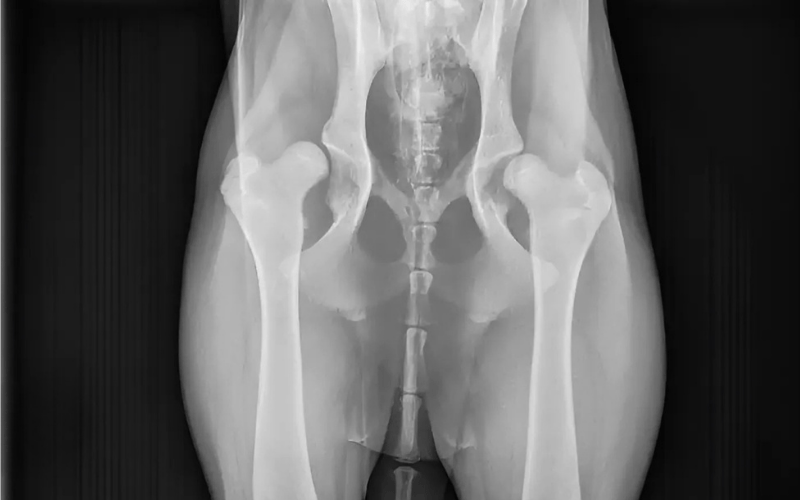

Wie regelmatig honden met heupdysplasie behandelt, weet hoe ingrijpend de traditionele chirurgische opties kunnen zijn. Bij ernstige vormen is een bekkenkanteling vaak onvermijdelijk: een zware ingreep met drie zaagsneden en een pittige revalidatieperiode per heup. Voor de hond én het baasje niet niks. Dat moest anders kunnen, dachten onderzoekers van de faculteit Diergeneeskunde en het UMC Utrecht. En dus begonnen ze samen aan de ontwikkeling van een alternatief: een 3D-geprint titanium implantaat dat de heupkom verlengt met een extra randje.

De nieuwe techniek is ontwikkeld én direct toegepast bij honden die in de kliniek kwamen met heupdysplasie – echte patiënten dus, geen proefdieren. Zeventig honden zijn inmiddels geopereerd met deze methode. Elke patiënt kreeg een implantaat op maat, gebaseerd op CT-scans. En met succes: de meeste honden lopen dezelfde dag alweer rond in de kliniek en kunnen de dag erna naar huis. Honden van uiteenlopende groottes, van 15 tot 90 kilo, werden behandeld – vaak aan beide heupen in één operatie.